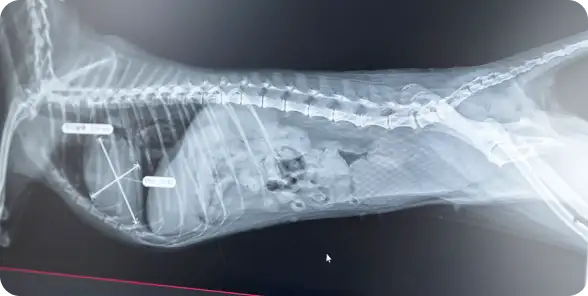

犬・猫・ハムスター・小鳥など、幅広い動物の診療に対応し、分かりやすい説明を心がけながら、最適な治療をご提案します。

しんどそうにしている、息が荒い、歩き方がおかしい、ケガ、下痢、嘔吐など、気になる症状があればご相談ください。

しこりがある、急に大きくなったなどの症状があればご相談ください。適切な検査を行い、高度な治療が必要な場合は、対応可能な病院をご紹介します。